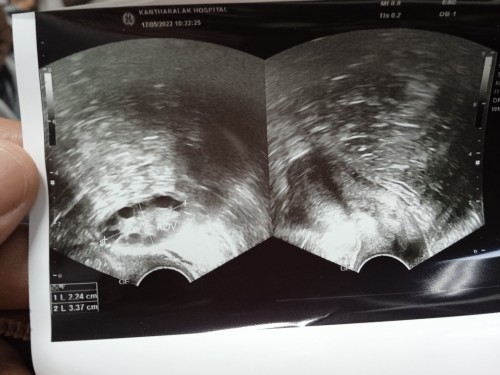

เมื่อวันที่17 ที่ผ่านมาหมอนัดซาวด์ และตรวจการตั้งครรภ์ ผลฉี่คือไม่ท้อง หมอเลยบอกว่าน้องน่าจะหลุด ตั้งแต่วันที่26เมษาที่ผ่านมาที่มีเลือดออก แต่ไม่ได้เจาะเลือดนะค่ะ แต่ในใบซาวแม่เห็นถุง หมอให้ยาปรับฮอโมนมาทาน แต่แม่ยังไม่ได้ทานค่ะ ว่าจะรอดูอีกสองอาทิตย์ ตอนนี้ถ้านับคือ6วีคกว่าๆ ควรกินยาหรือป่าวค่ะ แม่ๆคนไหนเจอถุงพร้อมหัวใจกี่วีคค่ะ น้ำหนักจาก68 เป็น70 ก้อยังมีคัดหน้าอก หัวนมก้อยังดำยุเลยค่ะ